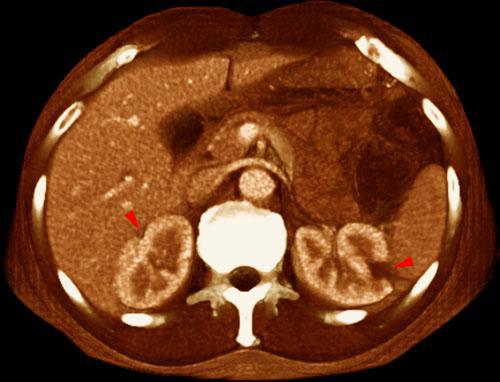

Infartos renales múltiples